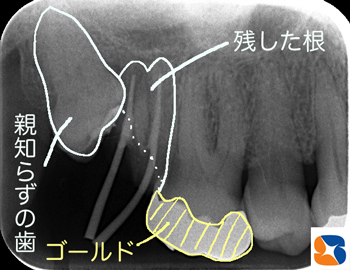

親知らずの周囲への悪影響

コラム「親知らずの周囲への悪影響」の画像